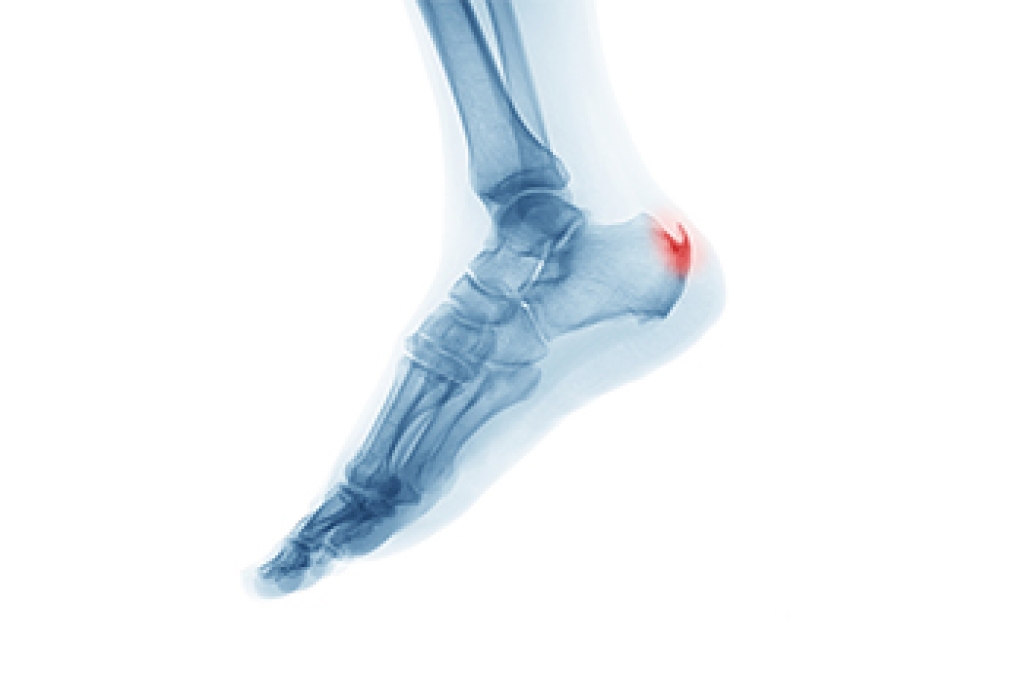

What Is a Heel Spur?

A heel spur is a bony growth that develops on the underside of the heel bone, often where the plantar fascia attaches. It typically forms over time as a response to ongoing stress or pressure on the foot. One of the main contributing factors is aging, as the tissues naturally lose elasticity and strength. Abnormal stress from repetitive activities, poor foot function, or walking patterns can place excessive strain on the heel. Carrying extra weight increases the load on the feet, which can lead to small tears in the plantar fascia. These micro-tears trigger inflammation and can encourage calcium deposits to build up, forming a spur. If you have heel pain, it is suggested that you schedule an appointment with a podiatrist who can accurately diagnose and treat heel spurs.

Heels Spurs

Heel spurs are formed by calcium deposits on the back of the foot where the heel is. This can also be caused by small fragments of bone breaking off one section of the foot, attaching onto the back of the foot. Heel spurs can also be bone growth on the back of the foot and may grow in the direction of the arch of the foot.

Older individuals usually suffer from heel spurs and pain sometimes intensifies with age. One of the main condition's spurs are related to is plantar fasciitis.